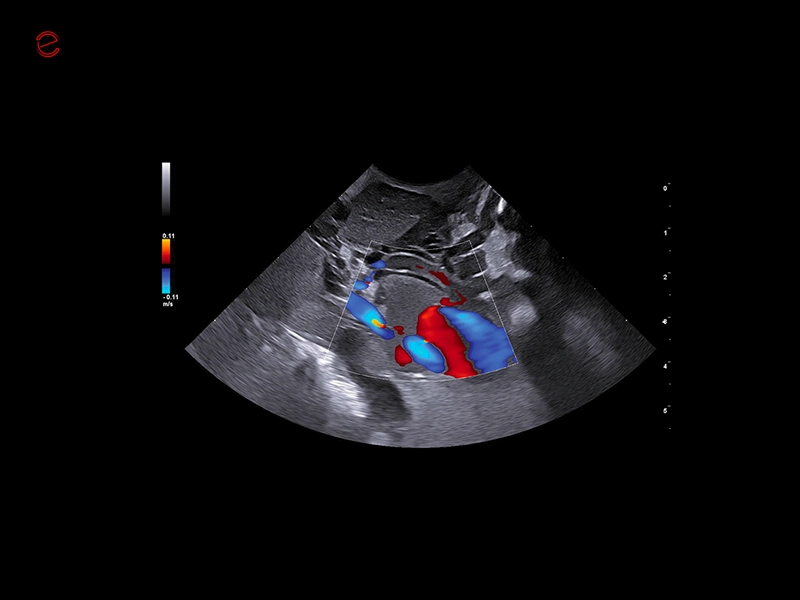

HIGH-RESOLUTION IMAGING IN ALL APPLICATIONS

Unmatched vision

Herons have exceptional eyesight, enabling them to detect subtle movements even in challenging conditions, making them highly effective hunters. Similarly, MyLab™Heron offers incredibly detailed and high-resolution imaging, in superficial areas as well as in deeper ones, thanks to the wide range of probes. All this makes it possible to scan from the smallest to the biggest animals in all applications covering general imaging, cardiology, musculoskeletal, reproduction, and ensuring unmatched clarity in all your examinations.